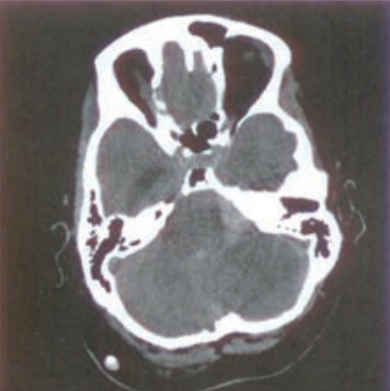

Na radiogramie TK głowy strzałką wskazano

A. zatokę sitową.

B. zbiornik wielki.

C. zatokę klinową.

D. przegrodę nosową.